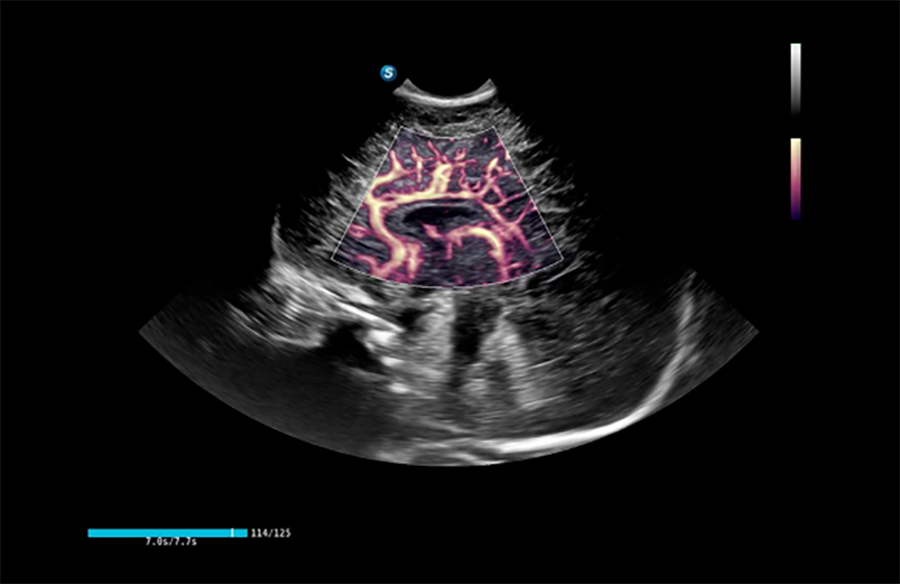

高帧率血流技术

清晰呈现复杂血管结构,可评估肿瘤良恶性、病变血流情况,为临床决策提供科学精准的血流影像依据。